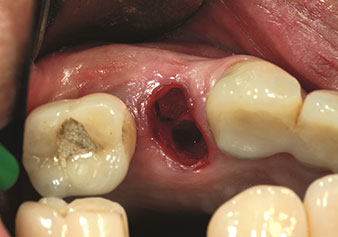

Un’applicazione che viene spesso sottovalutata è l’estrazione atraumatica di radici di denti o frammenti di radici nell’ambito della gestione alveolare. I periotomi sottili, che sono attualmente disponibili in due versioni (EX1 ed EX2 di W&H), possono essere, inoltre, utilizzati per rimuovere con facilità denti che hanno precedentemente subito uno specifico trattamento endodontico o con radici anchilosate. Ne consegue l’estrazione di alveoli in cui i tessuti duro e molle sono entrambi completamente intatti in quanto è generalmente possibile evitare la riflessione.

Ciò pone le basi ottimali per un trattamento con impianto immediato o successivo (Figure 1 e 2 inserite grazie alla gentile concessione del Dott. Torsten Conrad, Bingen a. Rhein).

Foto: © Dott. Torsten Conrad (Bingen a. Rhein)